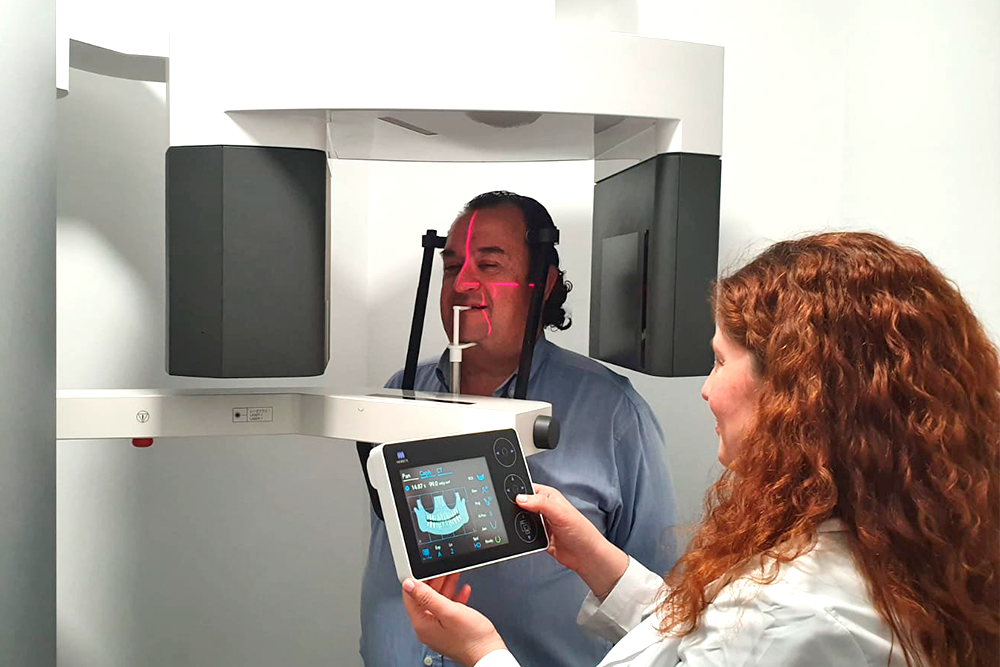

Instalaciones

Aula

Clínica